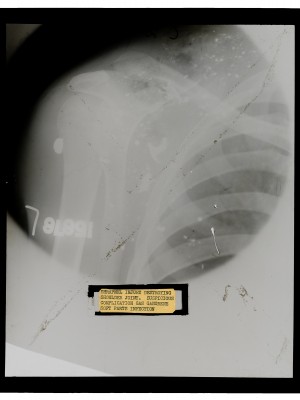

Ernst, Edwin Collection

Dr. Edwin Ernst, an only child born to St. Louis residents Charles and Catherine Ernst, was a notable Roentgenologist, a physician who specializes in radiological work. Dr. Ernst studied at Washington University in St. Louis and later at Moravian College in Bethlehem, Pennsylvania earning his advanced degrees. For two years he served as a resident physician at the St. Louis Mullanphy Hospital before leaving to pursue a private practice. When the United States formally entered the war in 1917, Ernst left St. Louis to become chief radiologist at Base Hospital 21. He was discharged honorably in 1919 with the citation of Major. His collection consist of x-ray images taken at Base Hospital 21 as well as drawings of radiological equipment and photographs.